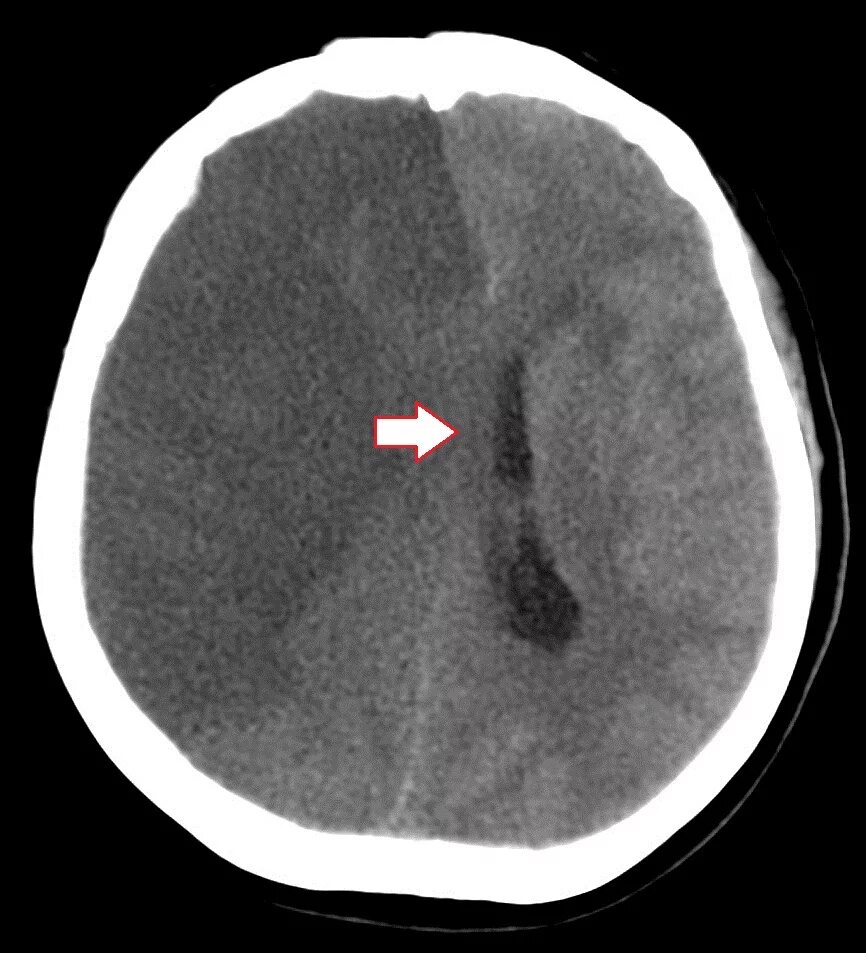

Отек головного мозга операции